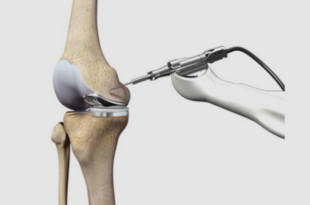

Read More »Robotic Knee Replacement in Chandigarh with Advanced Technology

Knee pain can really affect your life. Simple things like walking, climbing stairs or standing can become difficult. If you are looking for a treatment robotic knee replacement in Chandigarh is a good option. ARV Orthopedic Hospital uses technology and expert care to help patients regain mobility and live pain-free …

Read More »Best Robotic Knee Replacement Surgeon in Mumbai for Advanced Pain-Free Recovery

When it comes to your health, choosing the right robotic knee replacement surgeon in Mumbai can make a life-changing difference. Knee pain can limit mobility, affect daily life, and reduce overall quality of living. At Kneebotics , patients receive world-class treatment supported by cutting-edge technology and experienced surgeons. This advanced …